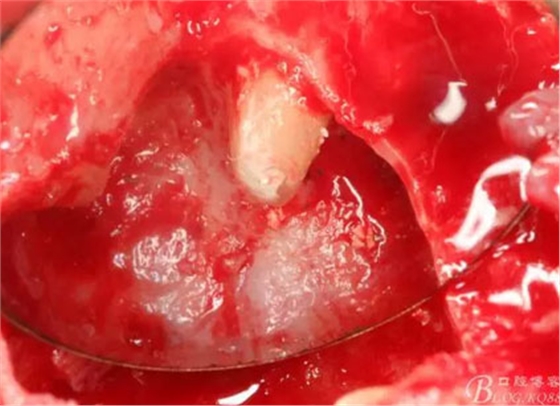

圖14.呼之欲出的囊腫

圖15.摘除的囊壁

圖16.囊壁摘除后22牙根懸浮在骨腔內(nèi)